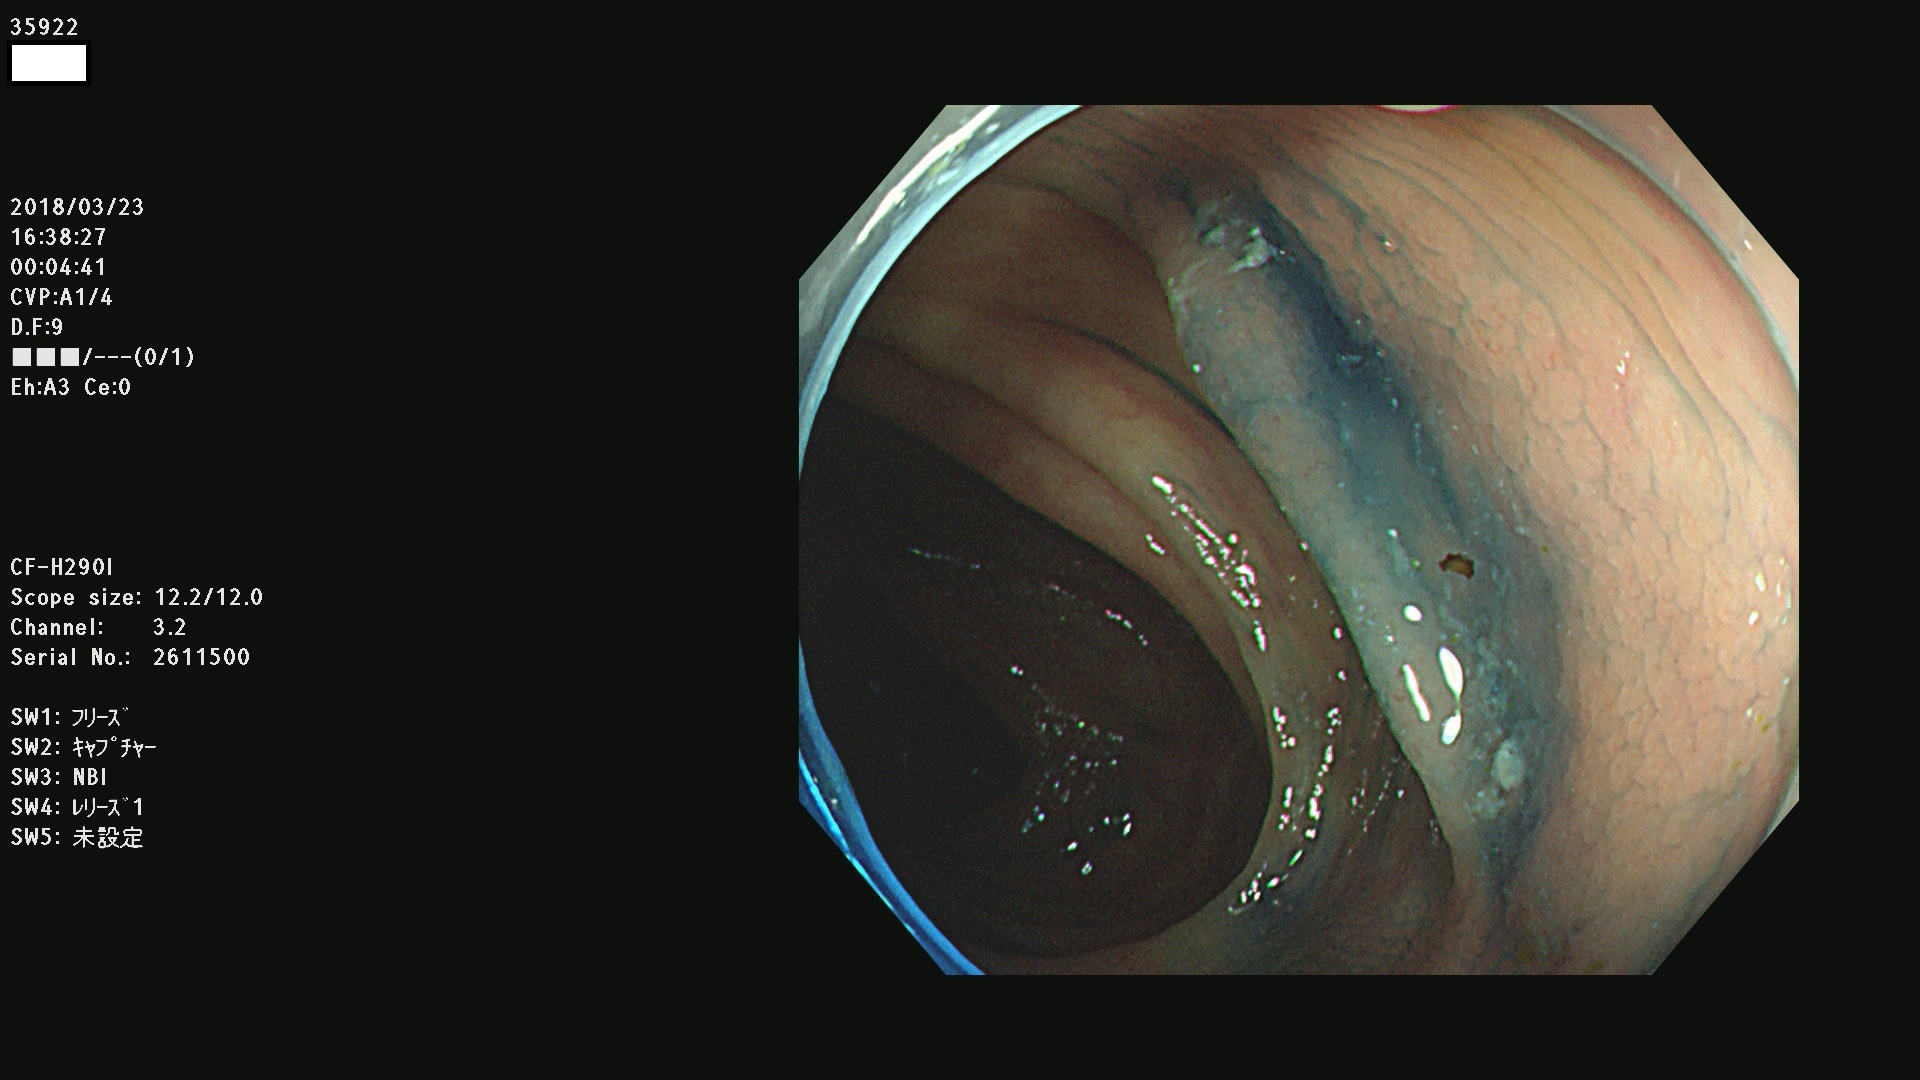

腺腫発見率43 % (カルテ番号 35900〜35999の100名の方の検査結果で集計)大腸癌検診最新情報

以下のカルテ番号の方に腺腫(Adenoma,Group3〜5)が見つかりました(集計法)

35900 35901 35904 35908 35912(SSA/Pのみ) 35914 35918 35922 35925 35926 35928 35931 35932 35933 35934 35937 35939 35943 35945 35947 35949 35951(SSA/Pのみ) 35952 35958 35959 35963 35964(SSA/Pのみ) 35965 35970 35972 35976(SSA/Pのみ) 35977 35978 35979(SSA/Pのみ) 35980(SSA/Pのみ) 35982 35983 35985 35991 35993 35995 35997 35999

発見困難で危険性の高い平坦型病変(上記100名より抽出) ![]()